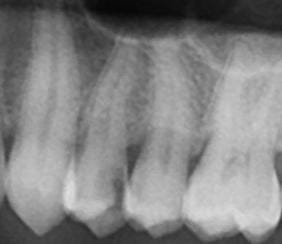

Busco el consejo de un especialista que me confirme la indicación de endodoncia en vista de la prueba que aporto

También, cuál sería la mejor manera de reconstruir la pieza, con o sin la realización de tratamiento de conductos; en particular, una alternativa al tratamiento habitual de perno y corona que teóricamente es eficaz en la protección de la pieza desvitalizada.

Desde mi punto de vista, no se aprecian los límites de la cámara pulpar, bien por la limitación 2D o por otro motivo. ¿Habría distancia de seguridad entre la reconstrucción y la pulpa para evitar daños posteriores?